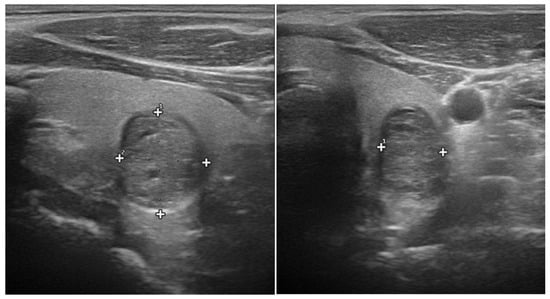

The taller-than-wide shape was assessed in longitudinal scans of nodules and defined as the antero-posterior/cranio-caudal ratio > 1, as shown in Figure 1. A longitudinal rather than transverse assessment allows for more strict definition of the taller-than-wide shape, since possible interference from rigid or bulky structures, such as trachea cartilage or supra-aortic vessels, which could lead to anteroposterior axis overestimation, is eliminated.

Figure 1. Example of taller-than-wide nodular shape, presented in ultrasound longitudinal scan (left side) and transverse scan (right side) of a thyroid lobe. The antero-posterior (vertical) axis (1) is superior in length to the longitudinal (horizontal) axis (2) of the nodular lesion.